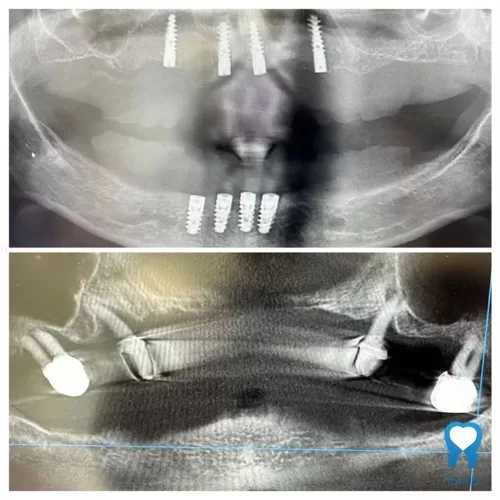

- Ugradnju nekoliko implantata u čeljust (obično 2 do 4)

- Postavljanje prečke koja služi kao osnova za pričvršćivanje proteze

- Ugradnja 2 do 4 implantata i postavljanje privremene proteze

Nakon cijeljenja implantata postavlja se trajna proteza na prečki